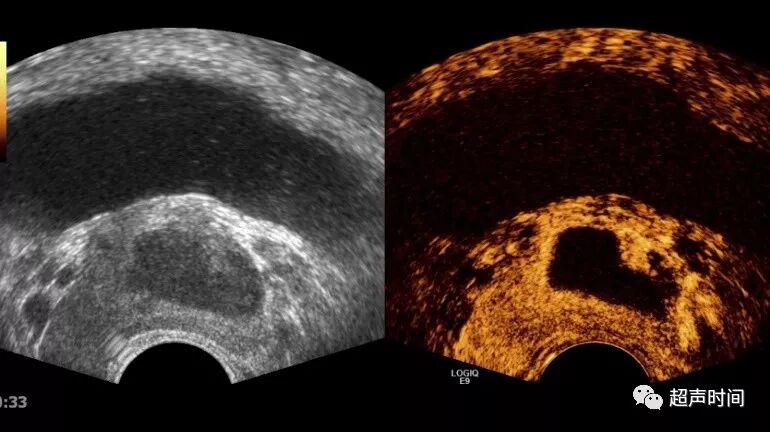

病理性囊性变:局部组织缺血坏死液化所致,表现为囊性变,多见前列腺中-重度增生和癌变的组织内。囊变可单发,也可多个,形态不规则,位于病变组织内(图 4)。

脓肿:多发生于炎症和结核,常发生在青壮年,前列腺增生不明显,囊肿暗区较大,直径 15~30 mm,囊液浑浊,呈低回声,二维超声难与低回声结节鉴别,超声造影可以确诊,并可在超声引导下穿刺引流(图 5)。

图 4 患者 80 岁,前列腺体积 120 cm³,增生病变区小囊肿(箭头)

图 5 前列腺脓肿。患者 45 岁,尿频尿痛。前列腺体积30 cm³,前列腺左侧叶内见大块低回声病灶,超声造影无增强